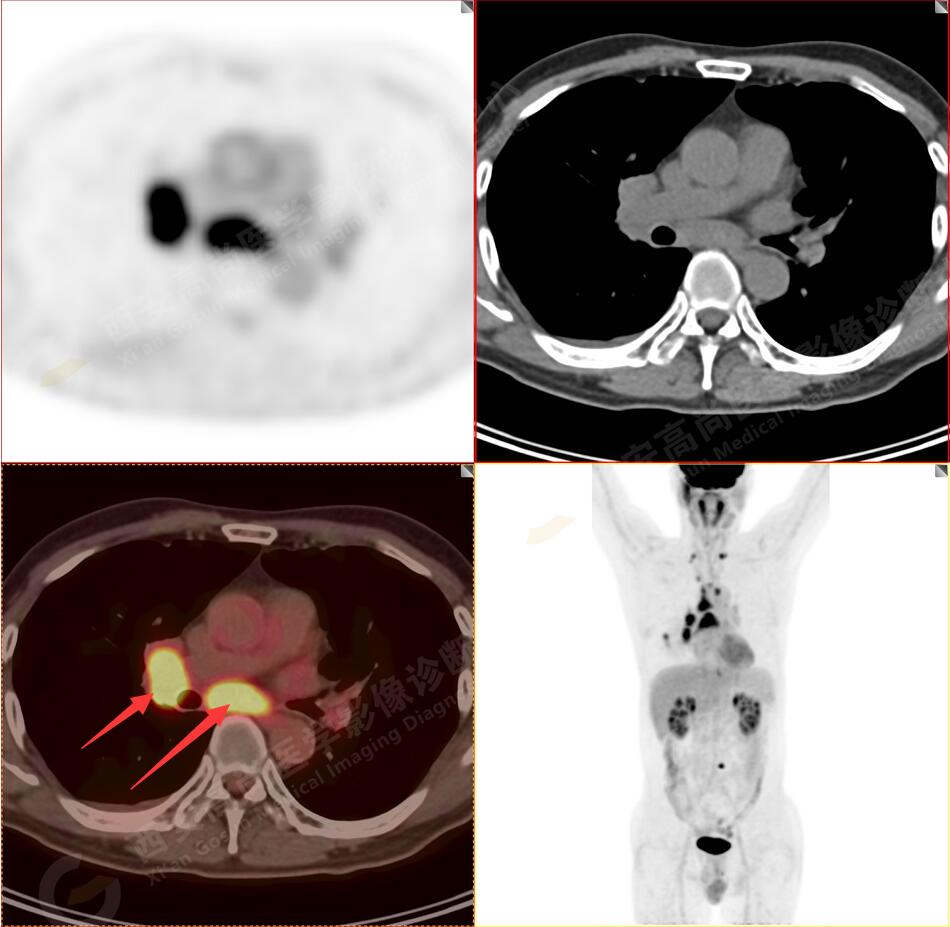

2.以下為全身多發(fā)轉(zhuǎn)移灶

4.右后胸膜輕度增厚,形成多個(gè)條狀軟組織病變,呈FDG代謝輕度異常增高,考慮為轉(zhuǎn)移性病變;右側(cè)胸腔微量積液。

5.腰4椎體左側(cè)緣溶骨性骨質(zhì)破壞,F(xiàn)DG代謝異常增高,考慮骨轉(zhuǎn)移瘤。

以上病變符合:T4N3M1c,ⅣB期(UICC/AJCC,2018年第8版肺癌TNM分期)。